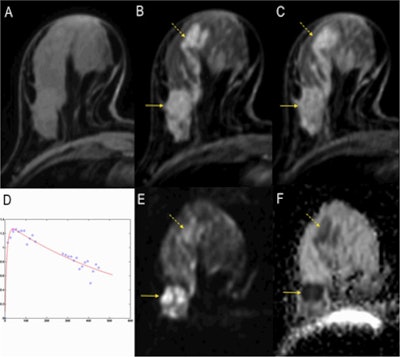

![A full examination at 3 tesla. A, B, and C: Precontrast T1-weighted imaging, early and delayed postcontrast scans depicting a mass (invasive ductal carcinoma, arrow) and associated clapped segmental nonmass enhancement (dashed arrow, ductal carcinoma in situ [DCIS]). D: The SI-time curve of the mass, indicating a malignant lesion by washout type 3 curve. E: The DWI image where the cancer lesions can be seen hyperintense similar to contrast-enhanced images. F: The apparent diffusion coeficient (ADC) map where the tumors are indicated by low signal intensity corresponding to typical restricted diffusion. Note that the signal of the invasive cancer is lower than that of the DCIS, confirming the ability of DWI to demonstrate quantitative differences in tissue microstructure not only able to diagnose cancer but also to differentiate invasive from noninvasive cancer. Images courtesy of Dr. Pascal Baltzer.](https://img.auntminnie.com/files/base/smg/all/image/2015/03/am.2015_03_04_22_11_00_218_2015_03_05_enhanced_MRI1.png?auto=format%2Ccompress&fit=max&q=70&w=400)